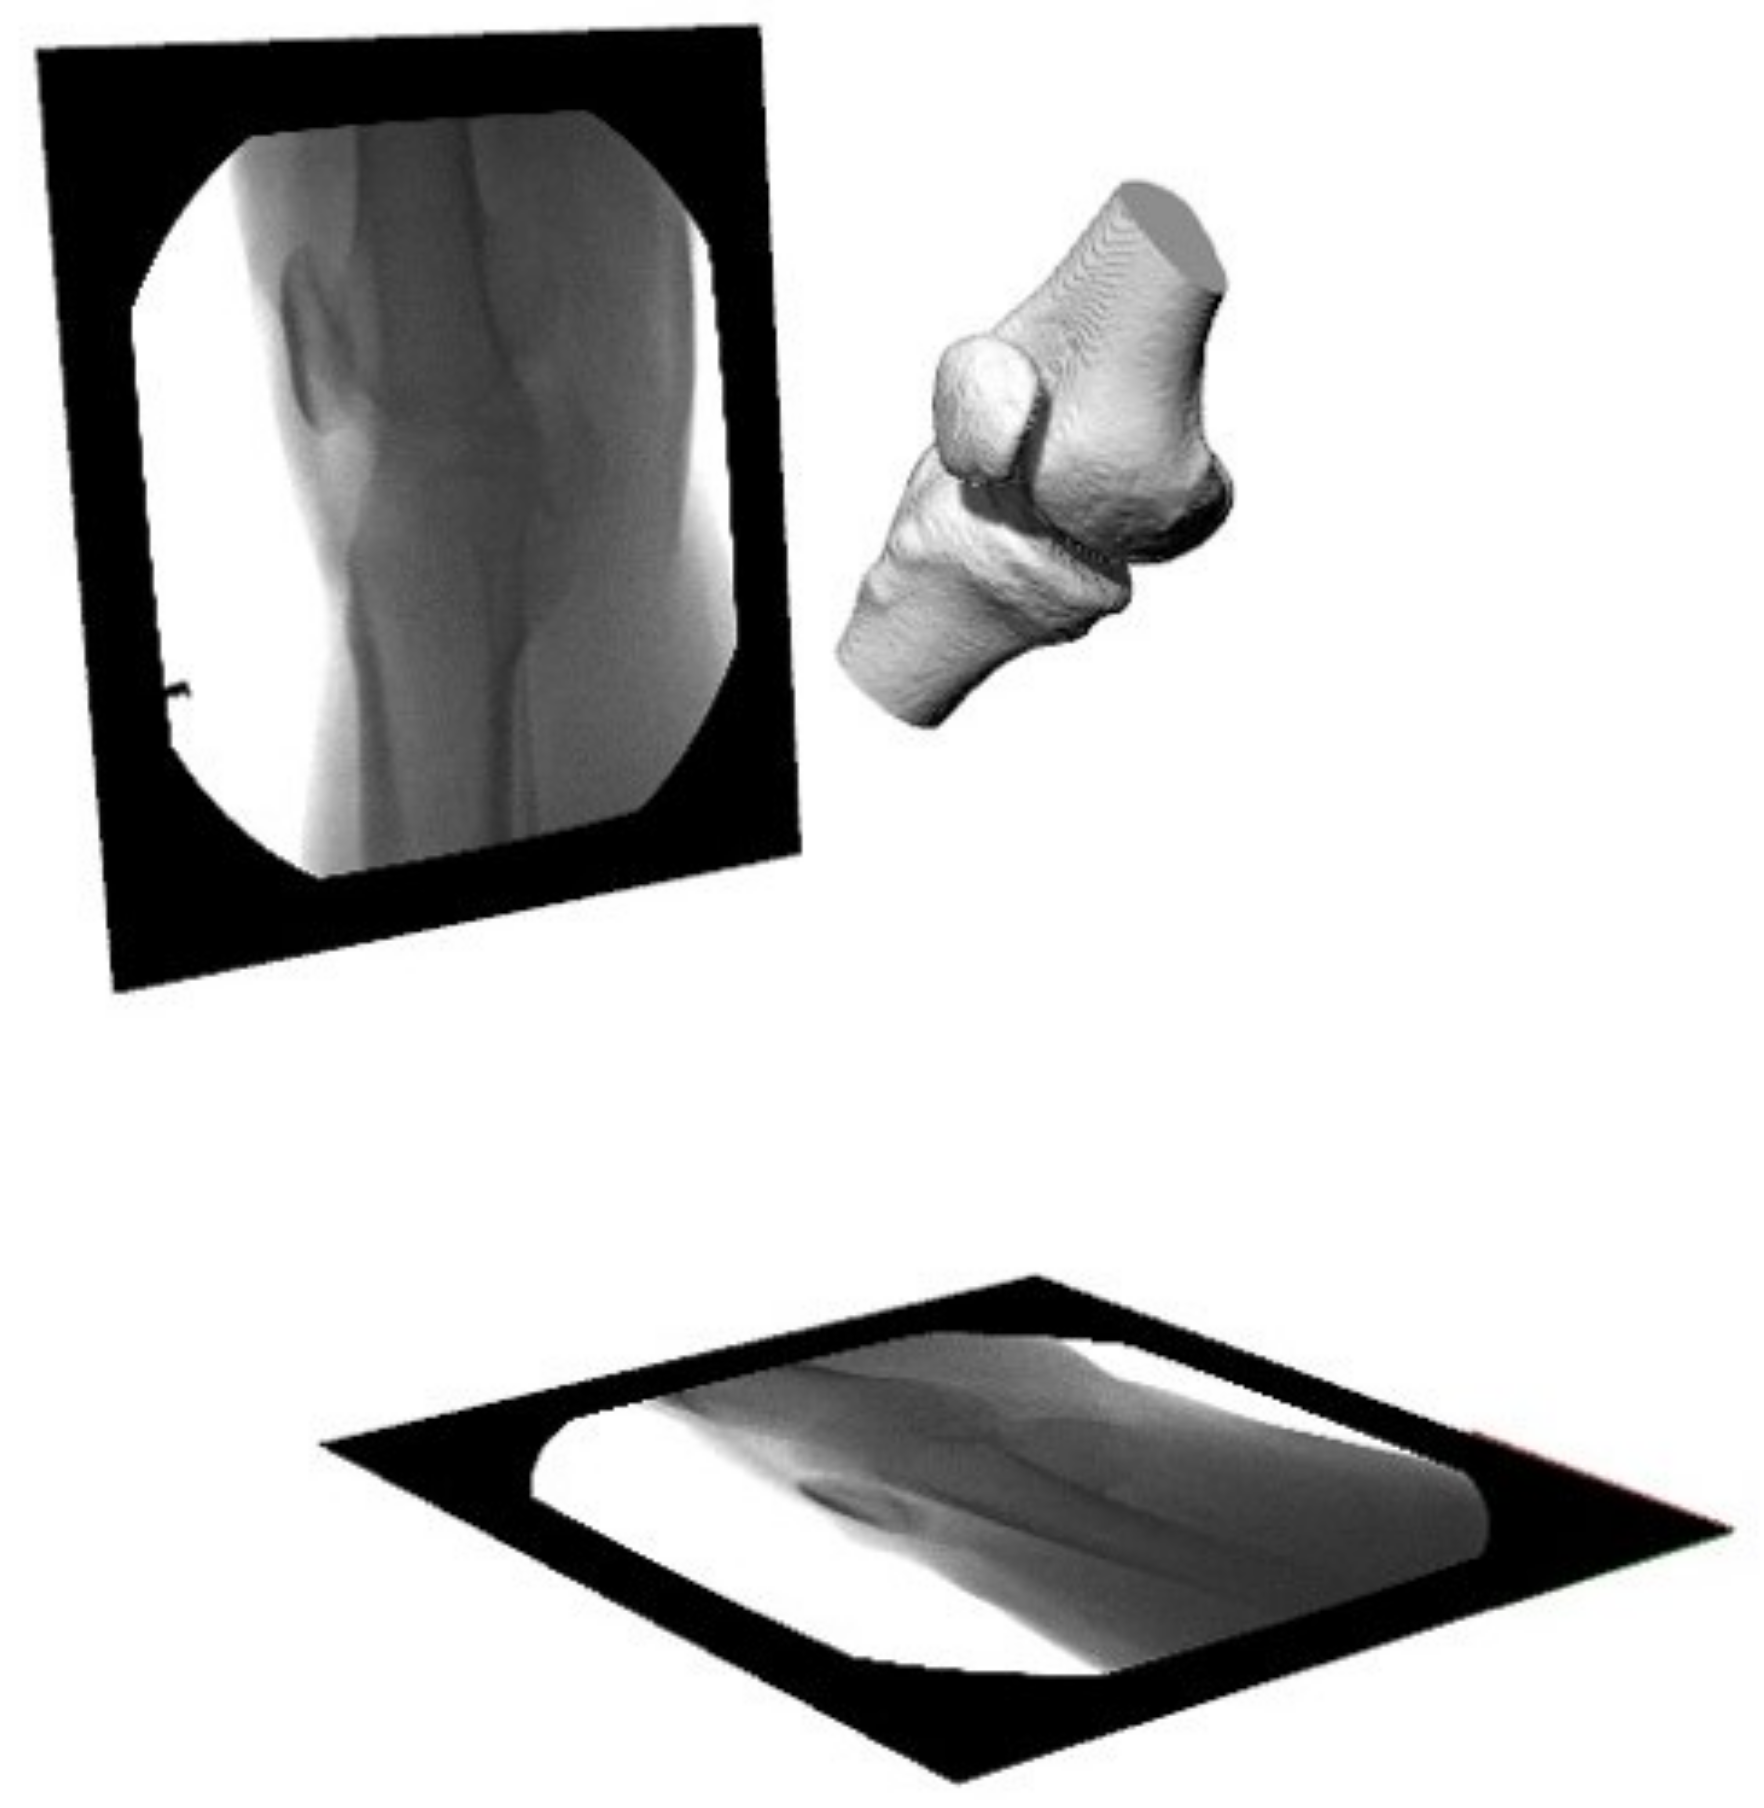

Patellofemoral pain (PFP) is the most frequent cause of knee pain. It frequently occurs in teenagers, manual labourers, and athletes. Patellofemoral pain syndrome may be caused by overuse, injury, excess weight, a kneecap that is not aligned correctly (patellar tracking disorder), or changes under the kneecap. Many researchers have shown that PFP is a precursor to early osteoarthritis [1,2], the leading cause of disability in the North American elderly population. Despite considerable efforts to improve the effectiveness of treatment interventions, 70% of individuals with PFP had persistent or recurrent symptoms 5–20 years after the intervention. Current interventions’ poor long-term outcomes highlight the necessity of better understanding the causes of PFP and its contributing factors. Generally speaking, patellar misalignment resulting in abnormal stress distribution is considered the primary mechanism for PFP [3,4]. However, the exact cause is unknown. This is due to the inability to evaluate in vivo three-dimensional (3D) patellofemoral joint (PFJ) motion during dynamic activities. Motion tracking in clinical studies is commonly based on surface marker video motion analysis, which suffers from measurement inaccuracy produced by soft tissue artefacts [5]. Therefore, researchers are investigating PFJ kinematics using 3D imaging modalities instead. In a paper by Esfandiarpour et al. [6], a new technique for real-time tracking of the knee bone structure using fluoroscopic imaging was proposed and tested. The methodology combined a computed tomography (CT) scan and bi-planar fluoroscopy techniques (see Figure 1a) to examine the knee motion with six degrees of freedom during the squatting of individuals with the syndrome and without. The calibration target shown in Figure 1b was used to correct the geometric distortion of the fluoroscopic images and determine the two imagers’ relative projection geometries. The calibration target was placed close to each image intensifier. A calibration algorithm compensated for radial distortions by using a matrix of small stainless steel spheres located at known positions, as shown in Figure 1c. Each image intensifier was independently corrected by using a radial distortion model. Then, an orientation plate (Figure 1d) was placed in the shared image acquisition area and imaged with two fluoroscopic sensors. One can compute the imaging sensors’ relative positions and orientations using the two images. Tracking the relative positions and orientations of the bones in a knee (tibia, femur, and patella) over time requires that a set of 3D mesh templates (one for each bone) must be extracted from CT imaging and individually segmented by using a simple thresholding technique (see Figure 2). One must track the projected image into the two by-plane fluoroscopic sensors to compute each knee bone’s position and orientation relative to the X-ray source (see Figure 3). Knowing the projective transform between the X-ray source and the two sensors from calibration, one can then infer what position and orientation each bone must have to produce these two images. The fluoroscopic imaging system captured two X-ray videos of the knee bones during motion from orthogonal viewpoints; one can see the resulting video sequence in Figure 4. Using an iterative re-projection software from Innomotion, Inc. (Shanghai, China) (http://www.innomotion.biz/ (accessed on 20 June 2022)) called FluoMotion, one can infer the three bones’ positions and orientations from the two orthogonal fluoroscopic image sequences. In Figure 5, one can see the projection of the knee bones for one frame, and in Figure 6, one can see a block diagram of the 3D-to-2D registration algorithm used, which is very similar to the algorithm described in [7].

The training phase took 20 h on a GeForce 980 TI GPU and 5 h on a Geforce 1080 TI GPU. A 3D mesh was generated using a marching cube algorithm following training. In Figure 11a, one can see the mesh produced for one instance of the femur 3D mesh created by the 2.5D U-Net, and in Figure 11b, one can see its corresponding mesh from the SKI10 label map. Likewise, one can see the 3D mesh produced by U-Net in Figure 12a and the corresponding 3D mesh from the SKI-10 label map for the tibia in Figure 12b. In Figure 13a, one can see the mesh produced for one instance of the patella 3D mesh created by the 2.5D U-Net, and in Figure 13b, one can see its corresponding mesh from the UofA label map.

Figure 2. (a) Creation of 3D knee bone templates from a series of CT scans captured in the knee extension position. (b) Definition of the coordinate systems of the femur, the tibia, and the patella used to quantify the patellar tracking parameters and tibiofemoral joint angle: M, medial; L, lateral; A, anterior; P, posterior; TEA, trans-epicondylar axis.

Figure 11. Femur 3D mesh model produced by (a) U-net and (b) the SKI10 ground truth.

Figure 12. Tibia 3D mesh model produced by (a) U-Net and (b) the SKI10 ground truth.

Figure 13. Patella 3D mesh model produced by (a) U-Net and (b) the UofA ground truth.